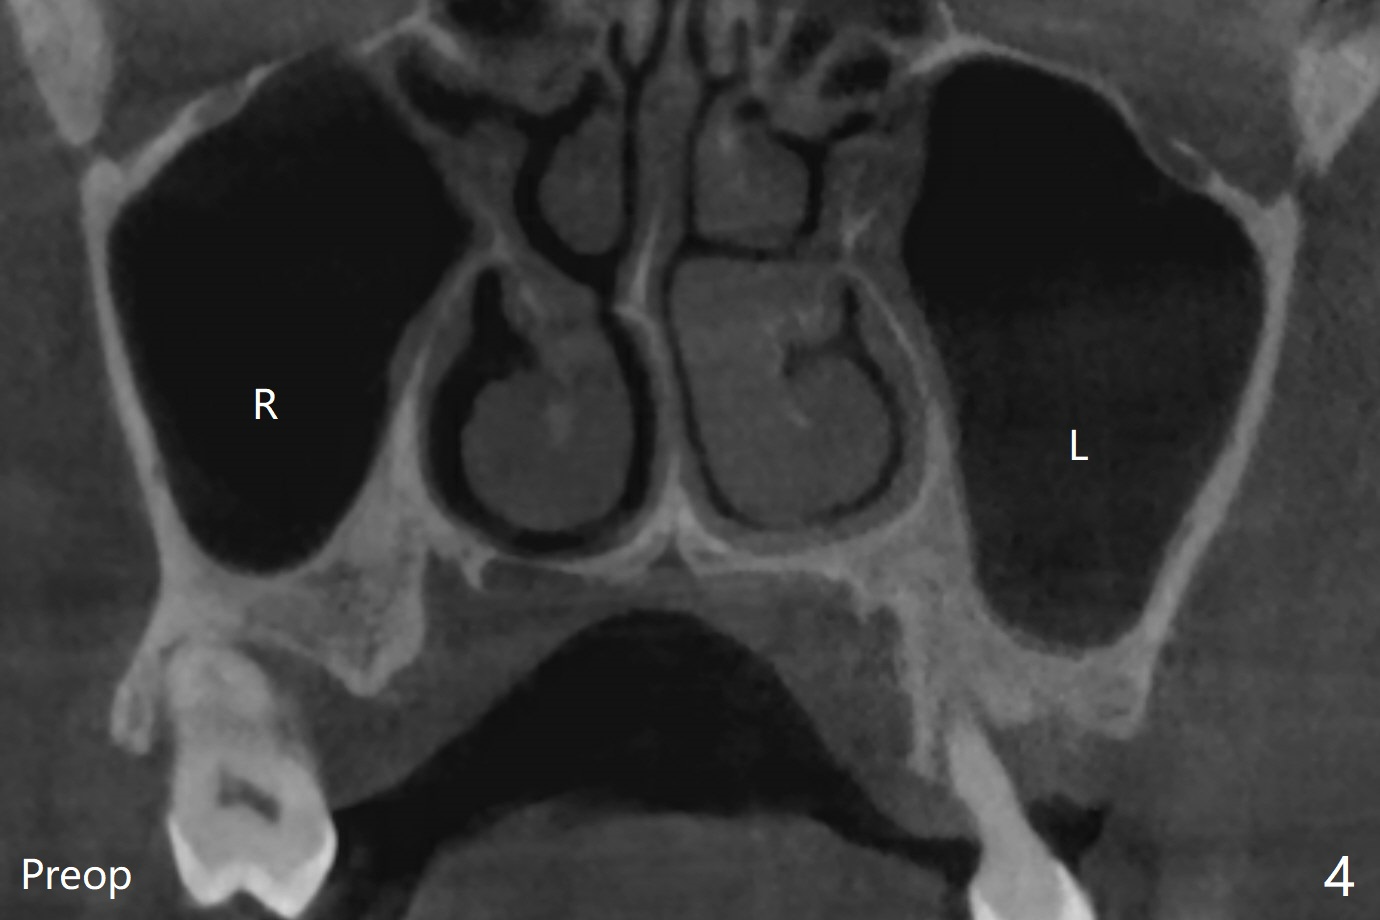

左上7完成初步钻洞,园钻头无法插入导板金属圈,用2.2毫米钻头钻深2毫米,窦膜似乎完整,在没有骨粉情况下,使用4x10毫米报废植体做上颌窦提升(图一),可能一下提升太多,窦膜破了,塞入两小块胶原膜,注入NovaBone

Putty (in

cartridge),植入短小植体(4.5x7毫米,原定(5x8.5毫米)图二),由于稳定性好,使用5.5毫米profile钻头后,放置5.5x4毫米愈合基台(图三)。术后病人没有什么上颌窦不适和分泌物。估计Novo

Bone在上颌窦里凝固了。其实左侧上颌窦粘膜术前增厚(图四,五:L),人工骨仿佛弥撒在上颌窦膜中(图六)。术后一周病人没有任何鼻窦症状。术后4.5月旋转愈合基台时,病人感到疼痛,终止取模(图七),两个月后复诊,做progressive loading。术后5.5月旋转愈合基台时,植体一起出来,但是上颌窦膜没有破,放置大一号植体(报废)扭力不够(图八),再大一号扭力可以(图九),放置愈合帽。由于邻牙长(图九:双箭头),牙周敷料逗留三周不掉(图十:P)。撤除后,伤口愈合正常。The